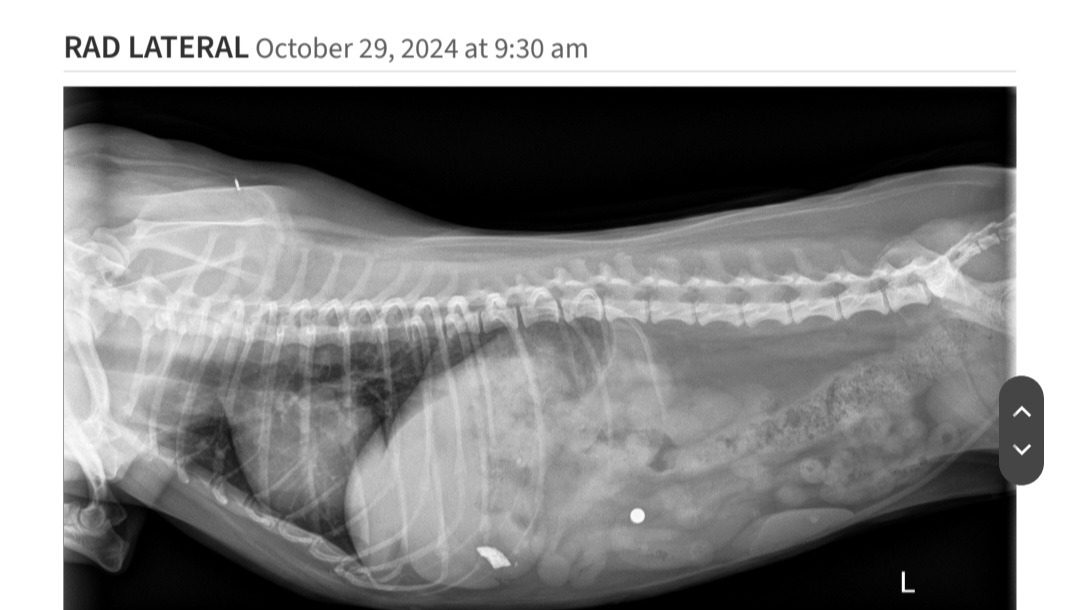

Little Freydis Potatis has been vomiting sporadically for a couple weeks, and we took her to the vet a few times to try and figure out why. When we took x rays on her most recent visit, we discovered that she swallowed an unknown object, and it's currently just vibing out in her stomach.